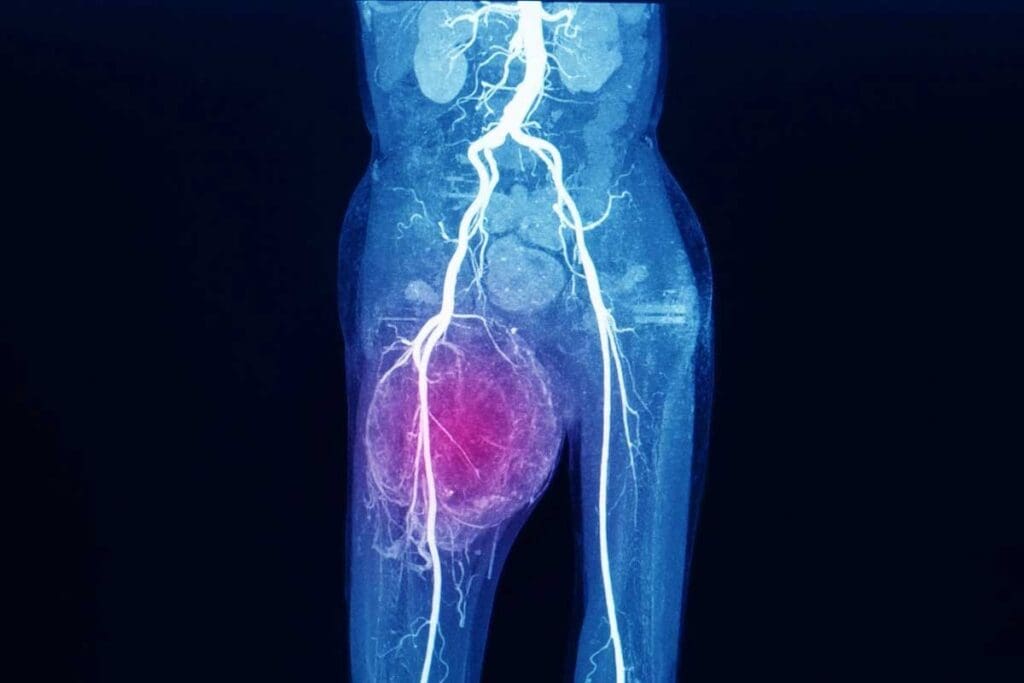

Discover what does ewing sarcoma look like on MRI and X-ray, and key imaging signs for diagnosis. Ewing sarcoma is a rare and aggressive bone cancer. It mainly affects kids and young adults. To diagnose it, doctors use X-rays and MRI.

- MRI provides detailed images that help in assessing the extent of the tumor.

MRI is key in diagnosing Ewing sarcoma. It gives clear images of soft tissue and bone marrow. These images help doctors understand the tumor’s size and type, which is important for treatment.

Soft Tissue Extension and Marrow Involvement on MRI

MRI is key in checking how far Ewing sarcoma has spread. It looks at soft tissue and marrow involvement. This helps doctors plan treatment accurately.

Evaluating Tumor Size and Boundaries

MRI shows the tumor size and where it starts and ends. It’s great for seeing how much soft tissue is involved. This helps doctors plan surgery and decide on extra treatments.

Detecting Marrow Infiltration

MRI is good at finding marrow infiltration. Ewing sarcoma often gets into the bone marrow. MRI shows how far it has spread. This helps doctors know how aggressive the tumor is and plan treatment.

Importance in Staging and Treatment Planning

Knowing about soft tissue and marrow involvement is key for staging Ewing sarcoma. Accurate staging helps predict how well a patient will do and guides treatment. It also helps plan surgery and decide on extra treatments.

In short, MRI is vital for diagnosing and planning treatment for Ewing sarcoma. It helps doctors understand how far the tumor has spread.